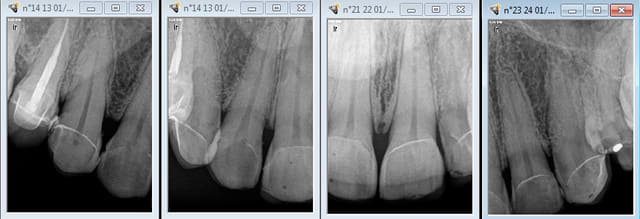

J'ai 300 ( environ) éléments cerecs à mon actif sur 2 ans, après j'ai arrêté de faire mumuse. -)))))

L'empreinte optique je connais un peu. Je suis convaincu de son avenir, mais je laisse les autres se casser le nez dessus le temps que la technologie se stabilise, chacun son tour. -)))))

Ceux là ont 8 ans.

Capture d e cran 2015 04 01 01.12 - Eugenol

Capture d e cran 2015 04 01 01.17 - Eugenol